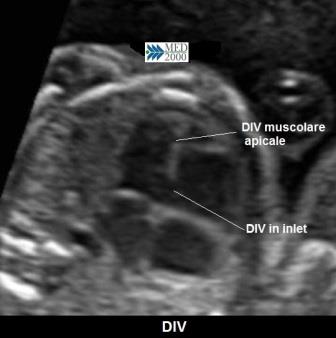

DIV perimembranosi: coinvolgono la parte membranosa del setto e quella muscolare ad essa adiacente; se l'interessamento muscolare si estende posteriormente verso il tratto di afflusso del setto vengono definiti "DIV in Inlet "; se l'interessamento muscolare si estende anteriormente verso il tratto di efflusso del setto vengono definiti "DIV in Outlet"; altre volte l'interessamento muscolare si estende inferiormente verso il tratto trabecolare del setto.

DIV muscolari: possono interessare qualsiasi porzione del setto (afflusso, efflusso, trabecolare).

DIV in inlet: il DIV appare come una soluzione di continuo della porzione membranosa/muscolare del setto; la scansione che meglio permette la visualizzazione di questo tipo di difetto è la 4-camere trasversa; difetti molto piccoli possono non essere evidenziabili; in questi casi può essere di aiuto l'ausilio del color-doppler col quale è possibile rilevare un flusso di tipo bidirezionale. Sono difetti di tipo evolutivo per cui quelli molto piccoli non sono evidenziabili nel II trimestre e spesso vengono visualizzati solo nel corso del III trimestre o alla nascita.